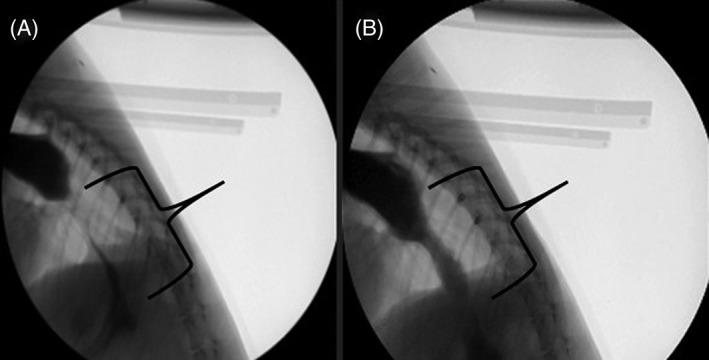

HYPOTHESIS/OBJECTIVES: To identify dogs with videofluoroscopic swallow study (VFSS) features of LES achalasia-like syndrome (LES-AS). We hypothesized that dogs with LES-AS could be distinguished from normal dogs using standardized VFSS criteria.

Retrospective study. One-hundred thirty dogs presented to the University of Missouri Veterinary Health Center (MU-VHC) between April 2015 and December 2017 for a free-feeding VFSS; 20 healthy dogs were included as controls. Swallow studies were evaluated for failure of the LES to relax during pharyngeal swallow (LES-AS). Affected dogs subsequently were evaluated using standardized criteria to identify metrics important for identifying and characterizing dogs with LES-AS.

Nineteen dogs with LES-AS were identified out of 130 VFSS. Megaesophagus was present in 14 of 19 (73.7%) dogs with LES-AS. A baseline esophageal fluid-line and "bird beak" were present in 68.4% (95% confidence interval [CI], 47.5%-89.3%) and 63.2% (95% CI, 41.5%-84.8%) of affected dogs, respectively. The esophagus was graded as acontractile (8/19), hypomotile (8/19), or hypermotile (3/19).

Dogs with LES-AS may successfully be identified by VFSS using a free-feeding protocol. These data are of critical clinical importance because a subpopulation of dogs with functional LES obstruction may be candidates for targeted intervention.

假设/目的:确定具有 LES 失弛缓症样综合征(LES-AS)的食管造影吞咽研究(VFSS)特征的犬。我们假设可以使用标准化的 VFSS 标准将具有 LES-AS 的犬与正常犬区分开来。

回顾性研究。2015 年 4 月至 2017 年 12 月,130 只犬在密苏里大学兽医学院就诊(MU-VHC)进行自由喂养 VFSS;20 只健康犬作为对照。吞咽研究评估 LES 在咽部吞咽期间是否无法放松(LES-AS)。受影响的犬随后使用标准化标准进行评估,以确定识别和表征 LES-AS 犬的重要指标。

在 130 次 VFSS 中确定了 19 只具有 LES-AS 的犬。19 只 LES-AS 犬中有 14 只(73.7%)患有巨食管。68.4%(95%置信区间[CI],47.5%-89.3%)和 63.2%(95% CI,41.5%-84.8%)的受影响犬存在基线食管液体线和“鸟嘴”。食管被分级为无收缩(8/19)、低动力(8/19)或高动力(3/19)。

LES-AS 犬可通过使用自由喂养方案的 VFSS 成功识别。这些数据具有重要的临床意义,因为功能性 LES 阻塞的犬亚群可能是靶向干预的候选者。